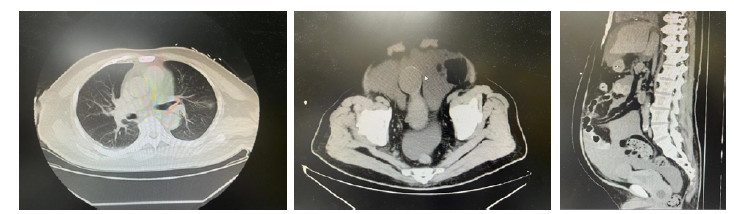

患者男性,79岁,因间断腹痛28 d,呼吸困难伴意识障碍1 d来诊。患者28 d前出现下腹痛,程度剧烈,可持续数小时,查腹盆腔CT提示右肾囊肿膀胱前上方低密度影-脐尿管囊肿可能;前列腺肥大。1周前出现胸闷、气短、腹泻。入院前1天出现呼吸困难,伴腹胀,伴尿量减少,逐渐出现意识障碍,救护车送至外院。就诊时下颌式呼吸、昏迷,外周氧饱和度74%(未吸氧),给予气管插管、呼吸机辅助通气后,神志好转,转来本院。完善腹腔穿刺引流,引流淡黄色微混腹水2 000 mL,腹水化验比重1.013,细胞总数1 230/μL,白细胞数230/μL,多核细胞百分数40%,单个核细胞百分数60%,葡萄糖25.3 mmol/L,总蛋白9.9 g/L,白蛋白4.9 g/L,球蛋白5 g/L,乳酸脱氢酶67 U/L,氯104 mmol/L,涂片找肿瘤细胞、细菌、真菌及结核菌均阴性。既往史:高血压病。20多天前诊断糖尿病。良性前列腺增生症。来诊时查体:体温37.8℃, 呼吸12次/min, 血压132/78 mmHg(1 mmHg=0.133 kPa),镇静状态,肺部查体未见异常,心率148次/min,律齐,各瓣膜听诊区未闻及杂音,腹部膨隆,腹肌紧张,叩诊浊音,压之可见痛苦表情。白细胞17.58×109/L, 中性粒细胞比例81.3%,血红蛋白158 g/L,血小板306×109/L,C反应蛋白62.69 mg/L,降钙素原1.6 ng/mL,BUN 36.03 μmol/L,血肌酐975 mmol/L,甲状旁腺激素113 pg/mL,N末端钠尿肽前体1 030 pg/mL,肌钙蛋白I < 0.01 ng/mL,尿常规尿蛋白2+, 尿红细胞4 725/mL,白细胞14/μl。胸部CT双肺渗出性病变,腹部CT腹盆腔大量积液、渗出,肝内多发低密度病变,右肾囊肿;膀胱导尿管置入,脐尿管囊肿可能;前列腺肥大(如图 1)。超声心动图心内结构大致正常,LVEF 62%,右室收缩功能正常。引流腹水1 000 mL后,夹闭腹引流管,大约20 min左右腹部膨隆,给予亚甲蓝尿管侧孔打入膀胱,1 min左右引流腹水变蓝(如图 2)。腹水肌酐:肌酐1 926 μmol/L。予哌拉西林舒巴坦治疗。入院第二天患者实施手术,术中可见膀胱表面可见一个直径4 cm脐尿管囊肿(膀胱憩室?),脐尿管囊肿(膀胱憩室?)表面可见一直径2 mm破口,有尿液缓慢渗出,从尿管向膀胱内注水,可见从破口向外喷水,考虑为脐尿管囊肿(膀胱憩室?)自发性破裂(如图 3),遂分离囊肿周围膀胱壁,沿脐尿管囊肿(膀胱憩室?)与膀胱交界处将脐尿管囊肿(膀胱憩室?)完整切除,可见脐尿管囊肿(膀胱憩室?)底部有小孔与膀胱相通,予以缝合膀胱。术后病理提示送检囊壁组织被覆尿路上皮,周围缺乏固有肌层,符合膀胱憩室。第3天血肌酐恢复至376 mmol/L,第4天血肌酐恢复至128 mmol/L,第5天,患者拔除气管导管,12 d后患者出院。

图 1 患者入院时胸腹部CT表现